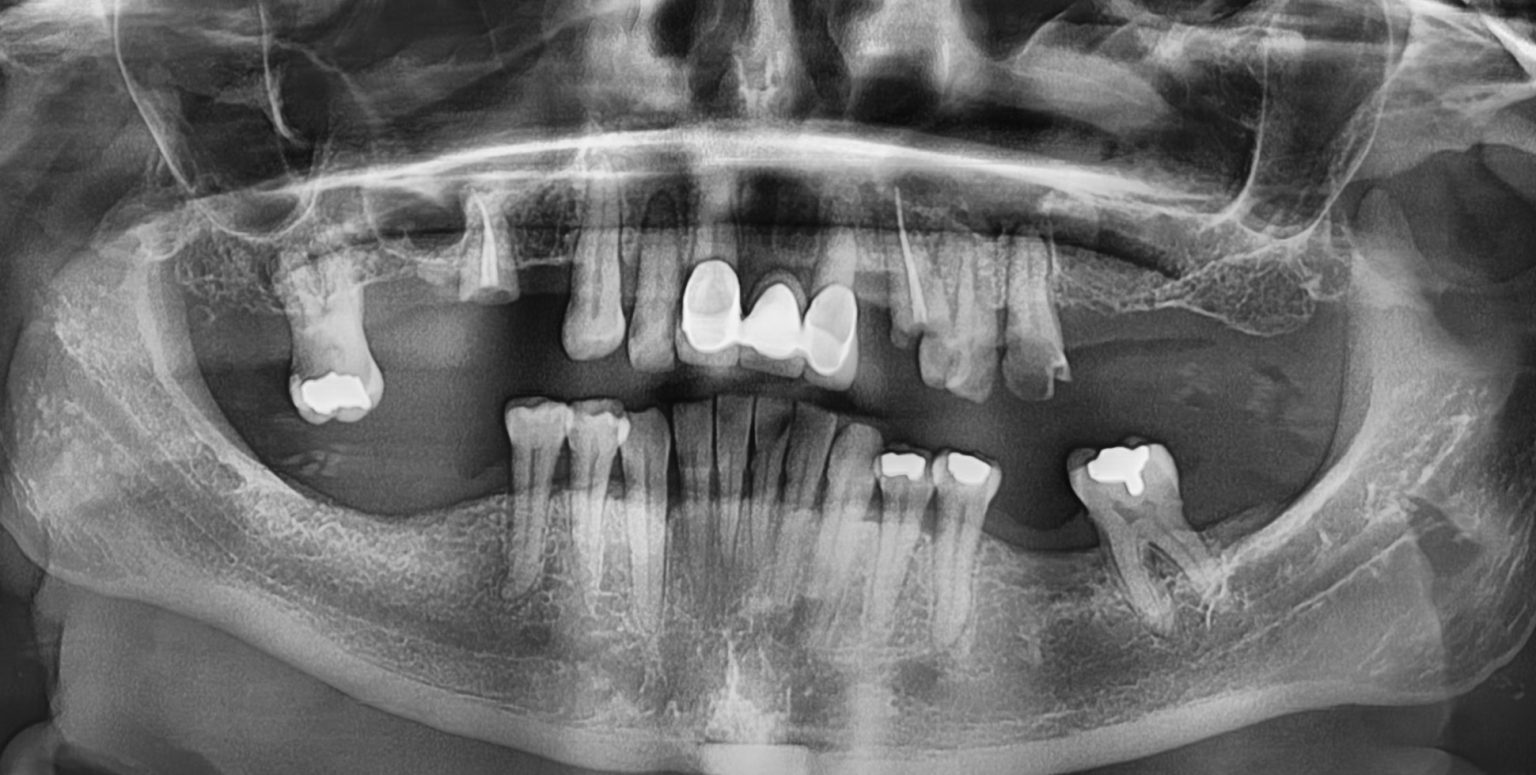

Teeth-In-A-Day is a revolutionary dental implant procedure that allows you to walk into the clinic with missing or failing teeth and leave the very same day with a beautiful, fully functional smile. In just one appointment, our expert implant dentist can place four strategically positioned dental implants and attach a fixed bridge, restoring your confidence instantly.

In its most advanced application, Teeth-In-A-Day can replace an entire set of teeth- upper, lower, or both- with implants and a non-removable set of natural-looking teeth in just 24 hours. This technique can also be used for replacing a single missing tooth without the lengthy wait times of traditional implants.